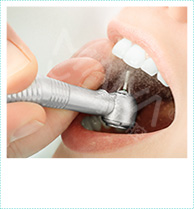

牙周深层维护费用